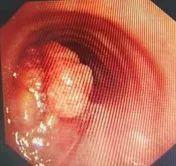

肿瘤几乎塞满了气管

“放松,放松”,陈晓峰让父子俩先平复下来,仔细了解患者病情。这是一位73岁的老人,气管里生了一个3.5cm的巨大恶性肿瘤,几乎塞满了整个气管,导致老先生几乎无法呼吸,随时可能因为窒息失去生命。